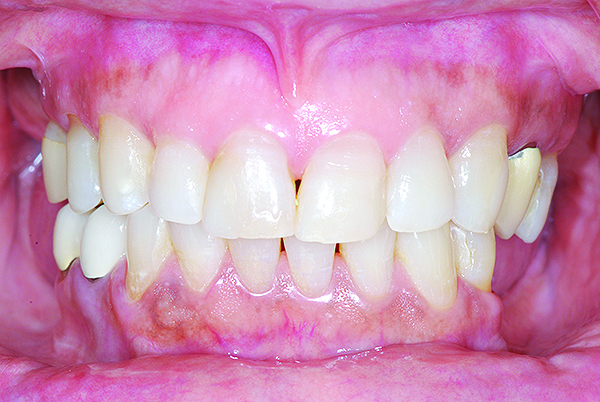

A 65-year-old Caucasian male presented for treatment at the University of North Carolina Dental Faculty Practice. The patient’s chief complaint was the appearance of his teeth, which looked short and had insufficient display when he smiled. The patient was partially edentulous in both the maxillary and mandibular arches and was wearing a cast mandibular RPD and a maxillary interim acrylic RPD. Findings from the clinical and radiographic examinations revealed moderate tooth wear on the posterior teeth and prepared maxillary canines without overlying extracoronal restorations. The prepared teeth were discolored, but no caries was detected clinically when examined using a caries detection solution. Also, the maxillary right first premolar had a coronal fracture and significant tooth wear. The prepared canine teeth were vital with limited interocclusal clearance available for any restorative material at the existing OVD (Figure 14).

The patient’s existing removable prostheses were evaluated clinically. The prosthetic teeth on both RPDs were worn, and after the OVD was assessed with the existing removable prosthesis, it was determined to be reduced significantly. Before making any decision on the type of treatment, the choice was made to first correct the OVD with an interim esthetic overlay acetal resin RPD.

The overlay partial was seated clinically, and minor adjustments were made to allow for full seating and occlusal equilibration centric and eccentric positions (Figure 17).

Fig 14. Pre-operative condition. Notice prepared maxillary canines with limited interocclusal clearance at existing OVD mainly on the left side.

Figure 14